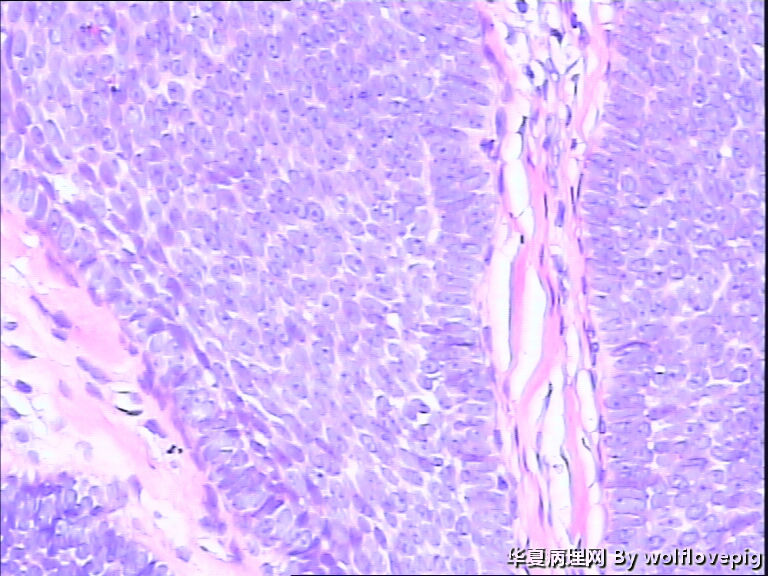

女,58y,右面部包块10年。灰白不整形带皮组织一块:2.3cm*1.5cm*0.3cm,切面有一灰白区域,质软,边界欠清。

图1

诊断考虑毛母细胞瘤,或毛发上皮瘤。

没有基底样物质,没有收缩裂隙,细胞异型不大,无明确核分裂像,考虑:附属器肿瘤,有点像汗腺来源的,如真皮导管瘤或螺旋瘤。请老师指点。

栅栏状外周结构,疏松的间质,基底细胞癌

与表皮无关,表皮无破溃,无收缩间隙-------不支持BCC  有角囊肿 促纤维增生-----支持毛发上皮瘤